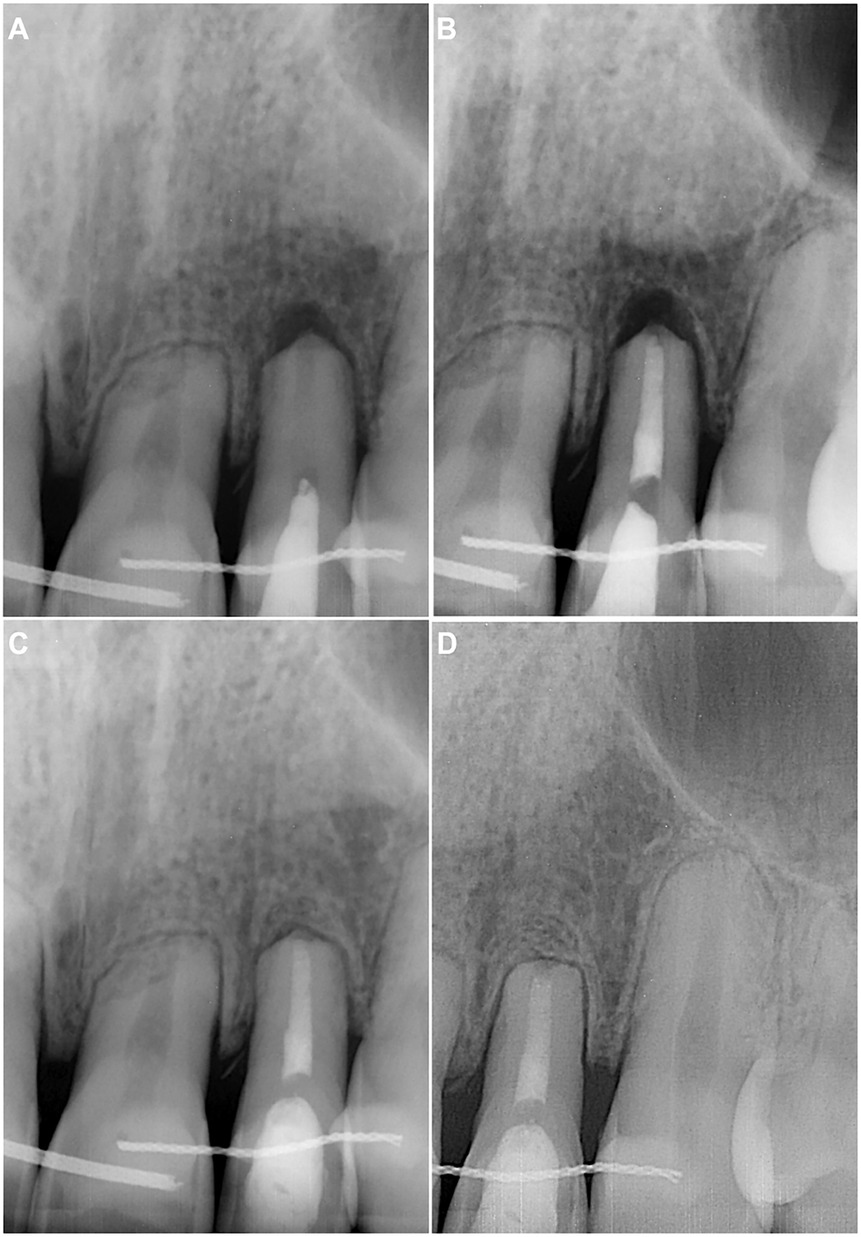

During the anamnesis at endodontist, the patient indicated that bleeding from the gingival sulcus was visible at tooth 22 instantly after the injury. The tooth was painful to touch and bitting, and the sharp edge of the broken fixed wire retainer was felt. The patient underwent orthodontic treatment for 3 years and was currently in the retention phase for 4 months. Upon examination, no extraoral and intraoral changes were observed (Figure 1A). No tenderness to percussion was detected for teeth 21 and 23, and the sensitivity to cold and heat stimulus was normal. Meanwhile, tooth 22 was slightly tender to percussion, with a negative response to cold and heat tests. The periapical radiograph revealed the advanced apical root resorption of teeth 21–23 and a uniformly widened periodontal ligament of tooth 22 (Figure 1B).

Figure 1. (A) Preoperative intraoral photo taken during the examination on the first visit. (B) Preoperative periapical radiograph revealing apical root resorption of teeth 21, 22, 23, and widened periodontal ligament of tooth 22. (C) Intraoperative periapical radiograph for WL determination with #45/0.02 K-File. (D) Postoperative periapical radiograph of cleaned and shaped root canal, filled with UltraCal XS paste. The access cavity was sealed with reinforced zinc oxide-eugenol restorative cement IRM.

After thorough anamnesis and clinical and radiological examination, the diagnosis of subluxation, along with pulp necrosis and apical periodontitis, was established for tooth 22. The endodontic treatment was initiated under local anaesthesia with 4% articaine and 1:100,000 epinephrine (Septanest, Septodont, Saint-Maur-des-Fosses, France). The procedure was carried out under a dental operating microscope (OPMI Pico; Carl Zeiss Meditec AG, Jena, Germany) which enabled inspection of the canal walls for cracks or fractures. The tooth was isolated with a rubber dam and Wedjets (Coltène/Whaledent, Langenau, Germany), and the crown was disinfected with an alcohol-based solution of 0.5% chlorhexidine. The endodontic access was prepared using high-speed Endo Access bur #1 (Dentsply Sirona, Ballaiques, Switzerland). The necrotic pulp was found in the pulp chamber and root canal.

The root canal working length (WL) was established using an apex locator and then confirmed radiographically (Figure 1C). The canal was shaped using hand files and the “apical box” technique up to #80/0.02 K-File (Dentsply Sirona, Ballaiques, Switzerland). After each instrument, the root canal was irrigated with 5 ml 3% sodium hypochlorite (NaOCl; Ultradent Products Inc., South Jordan, UT, USA) using disposable syringes and 29-G NaviTip needles (Ultradent Products Inc., South Jordan, UT, USA). At the end of shaping, a 5 ml 17% EDTA solution (Ultradent Products Inc., South Jordan, UT, USA) was used. The canal was then dried with sterile paper points and filled with calcium hydroxide paste UltraCal XS (Ultradent Products Inc., South Jordan, UT, USA) (Figure 1D). The endodontic access was sealed with intermediate restorative material IRM (Dentsply Sirona, Ballaiques, Switzerland). Finally, the broken retainer was fixed using light-cured resin-bonded composite Charisma (Kulzer GmbH, Hanau, Germany).